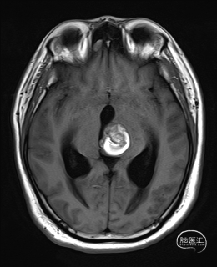

术前MRI检查

术前MRI检查提示左侧丘脑中脑海绵状血管瘤并卒中,梗阻性脑积水;

诊断:1.左侧丘脑中脑海绵状血管瘤并卒中,2.梗阻性脑积水;

根据MRI及DTI显示,只有在丘脑与上丘之间的点(dot)进入病变才可能在切除病变时最大程度保护神经功能,由于上述原因,该“点”在术中显露极其困难,虽有导航指引,电生理监测的条件下,对术者的耐心、技术、经验及体能依然是极大的挑战;

本例患者磁共振检查清晰显示病变位于左侧丘脑中脑区域,且位于丘脑内下方向中脑顶盖延续,病变的上部、前部、外侧部都有重要的神经组织,因此,手术从上方、前方、外侧方向切除病变均难以实施;